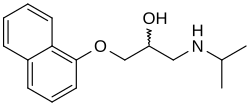

Non-selective beta blocker

- Propranolol

Beta blockers

The first beta blocker, propranolol, was introduced in the early 1960s by the winner of The Nobel Prize in Physiology or Medicine 1988- Sir James W. Black.[23] The drug was originally developed in order to induce a calm effect on the heart by blocking the beta receptor for adrenaline, treating a range of cardiovascular disorders.[23]